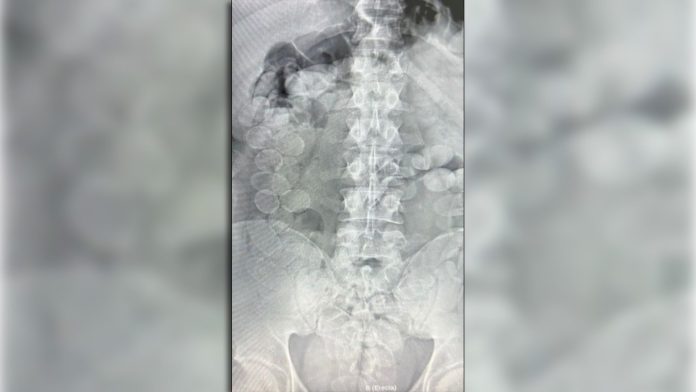

Bajo supervisión de profesionales de la salud, se practicaron placas radiográficas que confirmaron la presencia de cuerpos extraños en el tracto digestivo de los pasajeros. Posteriormente, los implicados expulsaron un total de 185 cápsulas.

Las pruebas realizadas por personal de Criminalística y Estudios Forenses determinaron que el contenido era clorhidrato de cocaína, sumando un peso total de 2 kilos 451 gramos. Los especialistas subrayaron que la ruptura de una sola cápsula podría haber resultado letal para los transportistas, un riesgo inherente a quienes actúan como “mulas”. Por disposición del magistrado interviniente, se ordenó el secuestro del estupefaciente y la detención de los ciudadanos involucrados.